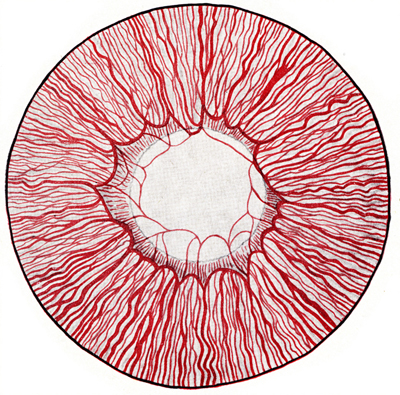

Diagrama de la apariencia del Iris y la Membrana Pupilar, de un feto humano de 7 meses,vista desde el frente.

Foto tomada de: Ida Mann ; The development of the Human Eye. 1969. Grune & Straton Inc N.Y

Foto de un Iris humano adulto, con residuos avasculares pigmentados de la membrana pupilar, viniendo del circulo menor. No tiene criptas.

Tomada del archivo fotografico del Dr. CB